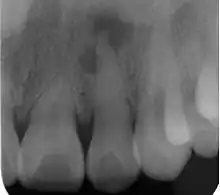

| Radiograph (X-ray) showing microdontia. Note also periapical lesion on the maxillary left lateral incisor. | |